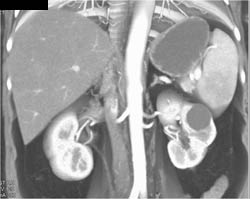

Antral Carcinoma in 3D